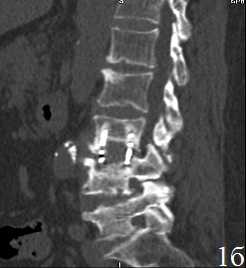

Рис. 2. Пациент У. Титановая блок-решетка с аутокостью через 6 месяцев (А) и через 12 месяцев (Б.) после операции. Отсутствие зоны резорбции вокруг имплантата без выраженного склероза, полная ассимиляция трансплантата с ложем

Через 12 месяцев после операции (табл. 4) в группе 1, несмотря на более выраженную резорбцию (6,43±1,06 мм), сагиттальный профиль позвоночника стабилизируется в сравнении с предыдущим периодом, при этом частичная стабилизация позвоночника появляется на фоне выраженного склероза за счет массивных краевых костных разрастаний. В то же время, в группе 2 у всех больных стабильность передней колонны обеспечивается полной ассимиляцией трансплантатов с ложем позвонков.